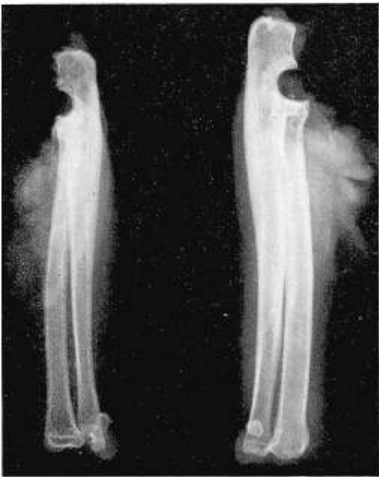

X射线显示,保留软骨组可见生长板和更平滑的骨端,而移除软骨组生长板缺失,骨端粗糙。

(左)仅关节离断与(右)关节离断加软骨切除的猫标本X光片。底部可见,在仅关节离断的标本中可见生长板及更光滑的末端,而关节离断加软骨切除的标本中则无生长板且末端粗糙。